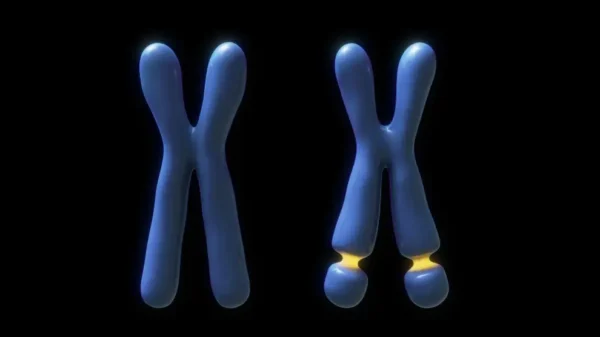

El síndrome del X frágil fue inicialmente identificado gracias a una alteración citogenética característica: una zona de fragilidad visible como una pequeña interrupción o estrechamiento en el extremo del brazo largo del cromosoma X. Esta anomalía estructural llamó la atención de los genetistas, ya que coincidía de manera consistente con individuos que presentaban discapacidad intelectual. Más adelante, los avances en biología molecular permitieron descubrir que esta fragilidad estaba relacionada con una expansión anormal de una secuencia repetitiva de tres nucleótidos —citosina-guanina-guanina (CGG)— ubicada cerca del gen denominado FMR1 (del inglés fragile X mental retardation 1), cuya función es esencial para el desarrollo y funcionamiento del sistema nervioso.

El diagnóstico del síndrome del X frágil ha evolucionado significativamente con el avance de las técnicas moleculares. En el pasado, la principal herramienta diagnóstica era el análisis citogenético, que permitía observar directamente el sitio frágil característico en el extremo del brazo largo del cromosoma X. Este método, aunque útil en su momento, presentaba limitaciones importantes: requería cultivos celulares especializados, tenía baja sensibilidad en algunos casos y no permitía una cuantificación precisa del número de repeticiones del triplete CGG en el gen FMR1, el verdadero responsable de la enfermedad.